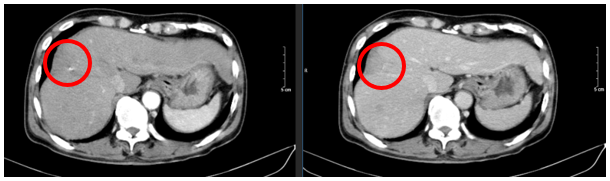

- Chụp cắt lớp vi tính ổ bụng:

Hình 1: Hình ảnh chụp cắt lớp vi tính ổ bụng: Nhu mô hạ phân thùy S7-8 có khối (vòng tròn đỏ) tỷ trọng hỗn hợp kích thước 81x51mm gồm phần tăng tỷ trọng của vật liệu can thiệp và nhiều bóng khí tạo thành ổ tụ khí trong nhu mô kèm phần hoại tử dạng dịch, không có huyết khối.